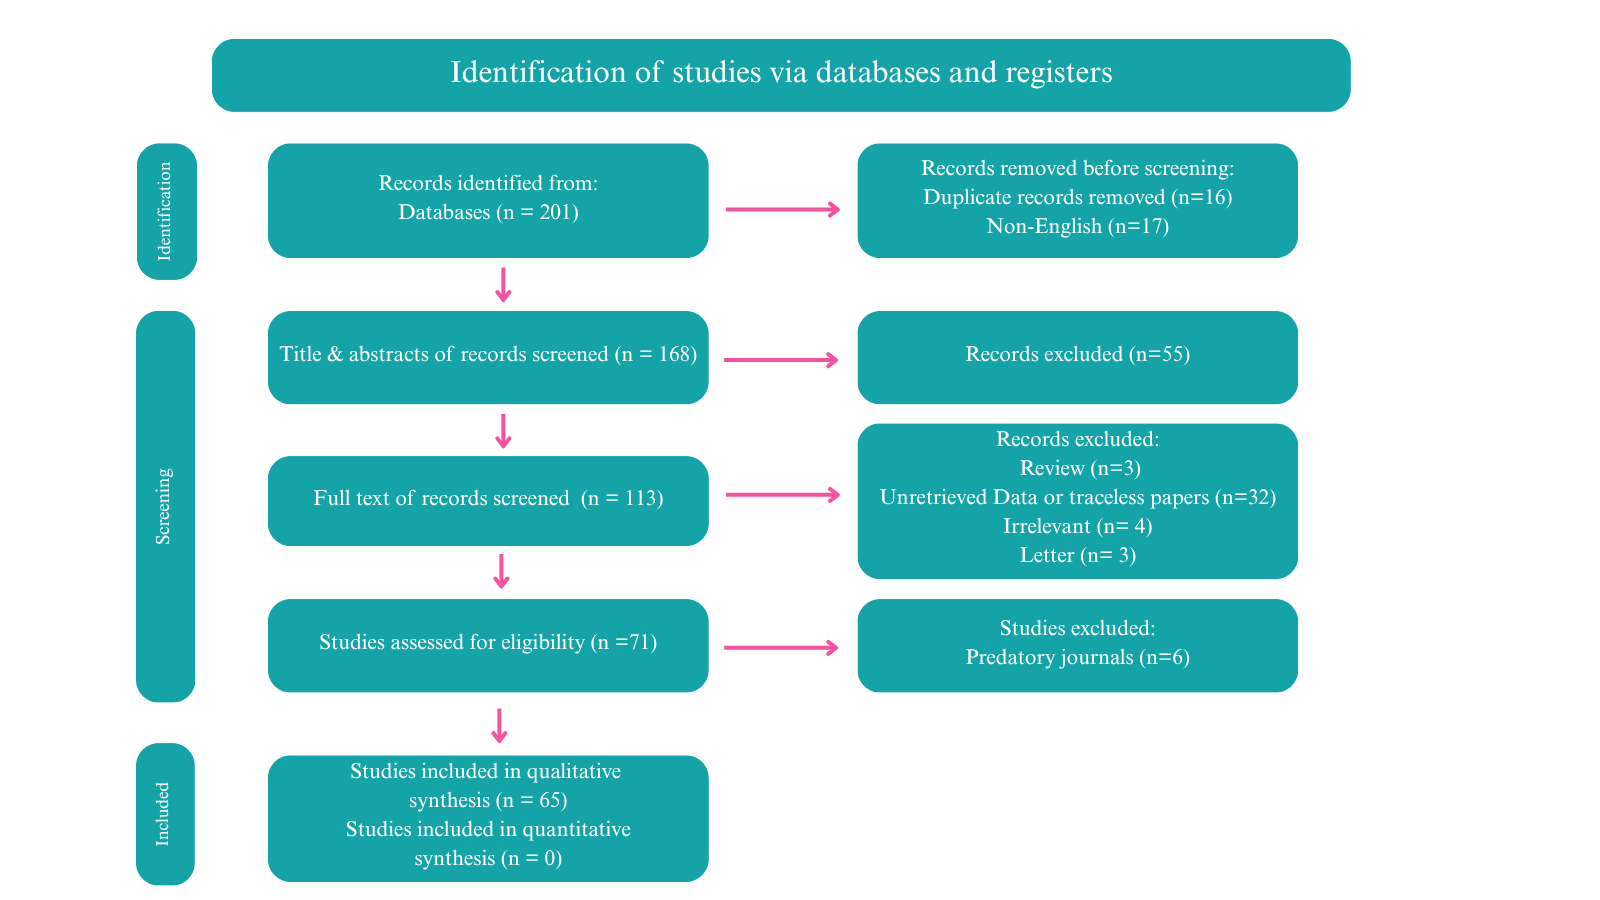

Thyroid function assessment revealed that the majority (7 cases ,63.6%) of patients were euthyroid (0.35-4.5µIU/mL), while two patients exhibited hyperthyroidism (<0.35 µIU/mL), and two of them had hypothyroidism (>4.5 µIU/mL). Ultrasound findings demonstrated left lobe and isthmus agenesis in eight cases (72.7%), while two cases (18.2%) exhibited isolated left lobe agenesis, and one patient exhibited isolated right lobe agenesis (9.1%) (Figures 1 and 2). The largest documented normal lobe measured 100 × 43 × 35 mm, whereas the smallest measured 15 × 6.9 × 7.9 mm. The follow-up period ranged from 4 to 48 months (Tables 1-3).